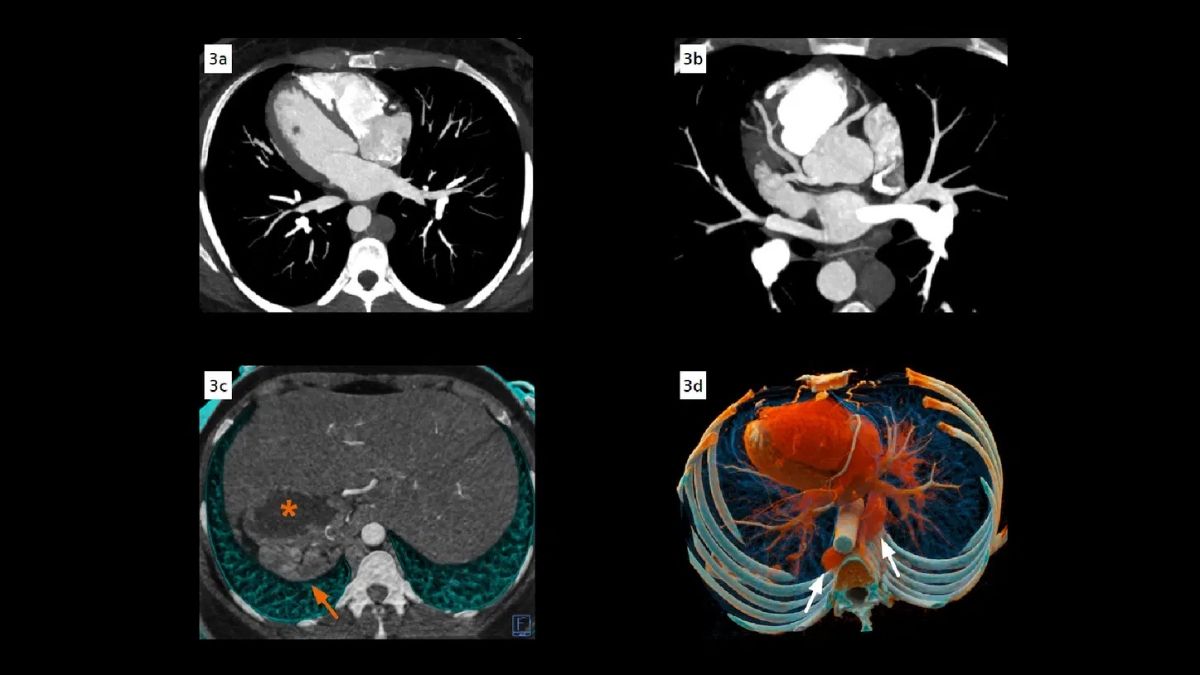

O’Hara precisó que, en su caso, se trataba de dextrocardia, una forma específica de situs inversus en la que el corazón se encuentra ubicado en el lado derecho del pecho.

El situs inversus es una condición genética poco frecuente en la que los órganos del tórax y del abdomen se desarrollan en una disposición especular, es decir, invertida con respecto a la anatomía estándar. Segun datos recuperados por People, afecta aproximadamente a una de cada 10.000 personas.